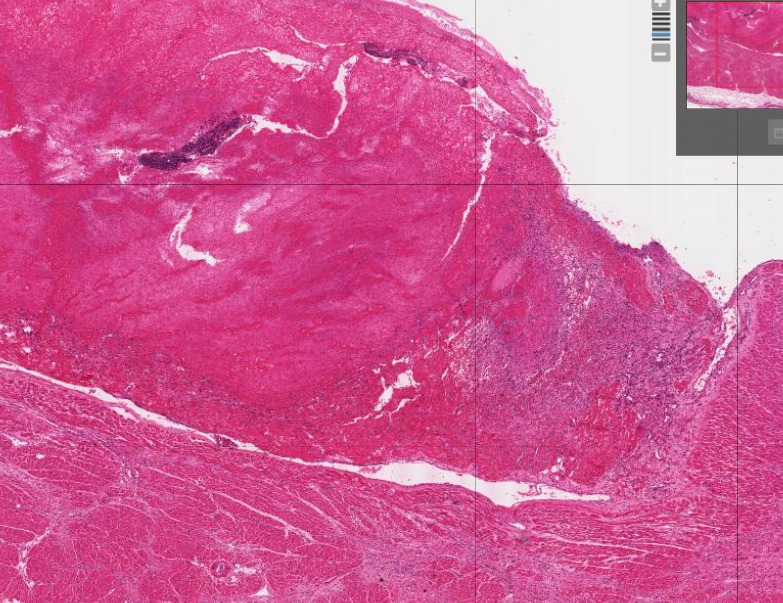

Organising anteroseptal transmural myocardial infarct with biventricular dilatation and thrombosis

Old and recent myocardial infarction with extensive left ventricular mural thrombosis. Note the pericarditis associated with the recent infarct, and the lines of Zahn in the thrombus.